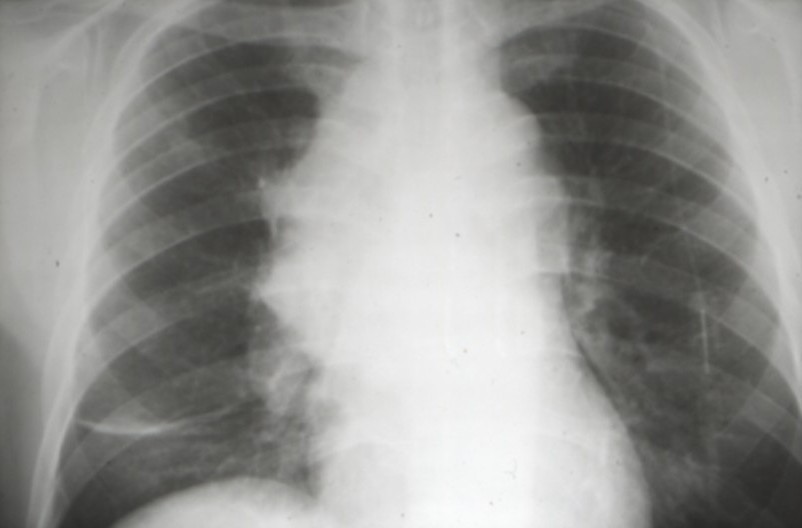

Cancers bronchiques